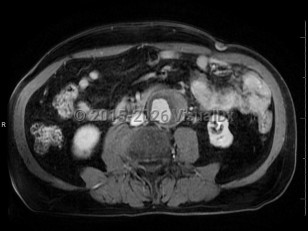

Pyogenic liver abscessPyogenic liver abscess